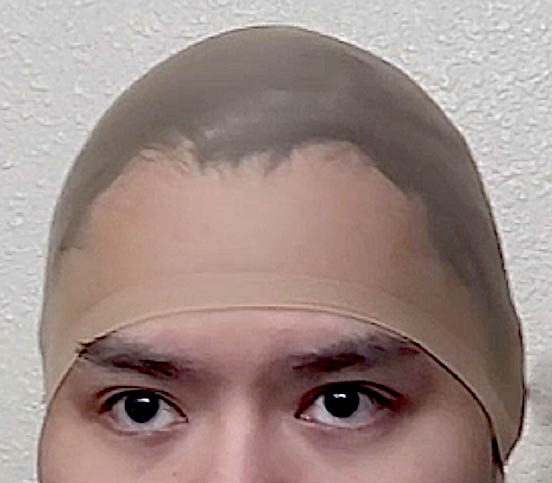

Patient 51

Desire for taller and rounder head shape.

Two stage custom skull implant augmentation technique.

Desire for taller and rounder head shape.

Two stage custom skull implant augmentation technique.